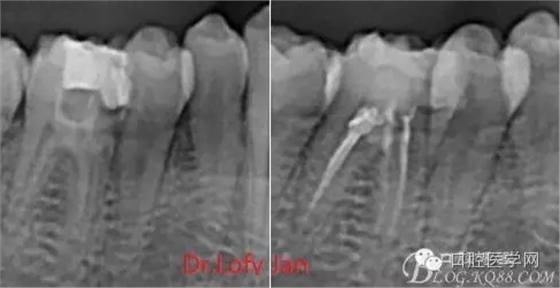

曲面斷層片在未試尖根管治療中的病例整理

前言:自己做的一些曲面斷層片在未試尖根管治療中的病例整理,發(fā)現(xiàn)問題很多包括自身的,技術(shù)的,還有設(shè)備的問題,予以總結(jié)整理并期待進(jìn)一步提高。

病例分析:曲面斷層片在x線輔助診斷與檢查中目前大多數(shù)文獻(xiàn)和著作都建議只能作為初診拍片檢查手段,不能作為終末疾病的確診與手術(shù)療效的評(píng)價(jià)指標(biāo),臨床大部分中小型門診都因?yàn)樵O(shè)備不齊全導(dǎo)致信息偏差很大。